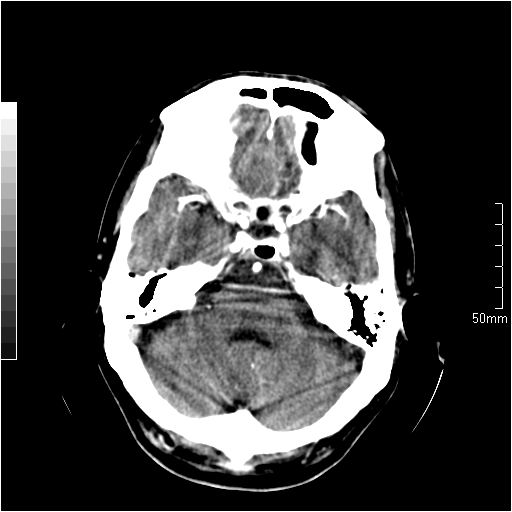

以下是引用天南地北在2007-6-25 12:39:00的发言:[br]有占位效应[br]支持术后复发

以下是引用zjzjr在2007-6-25 12:38:00的发言:[br]左侧复发,右侧转移。